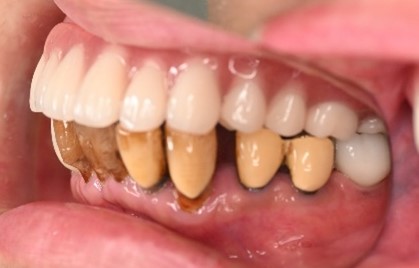

女性Tさん 50代(マグネット式入れ歯)

主訴

左上の犬歯が、グラグラして痛い

治療内容

他の歯も歯周病が進行していました。保存することができない歯が3本ありましたので、抜歯し、残った歯6本の歯周病治療をし、それらの歯を活用しマグネット式総入れ歯を入れました。

所感

マグネット式総入れ歯を活用し、もともとは反対交合でしたが、正常交合に改善することができました。

Before

赤丸は抜歯しました

After

【義歯を装着したところ】

【義歯を外したところ】

マグネット義歯

緑丸は組み込まれたマグネット